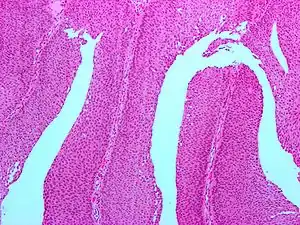

| Micrograph of a PUNLMP. Intermediate magnification. H&E stain. | |

Histologically, they have a papillary architecture with slender fibrovascular cores and rare basal mitoses. The papillae rarely fuse and uncommonly branch. Cytologically, they have uniform nuclear enlargement.